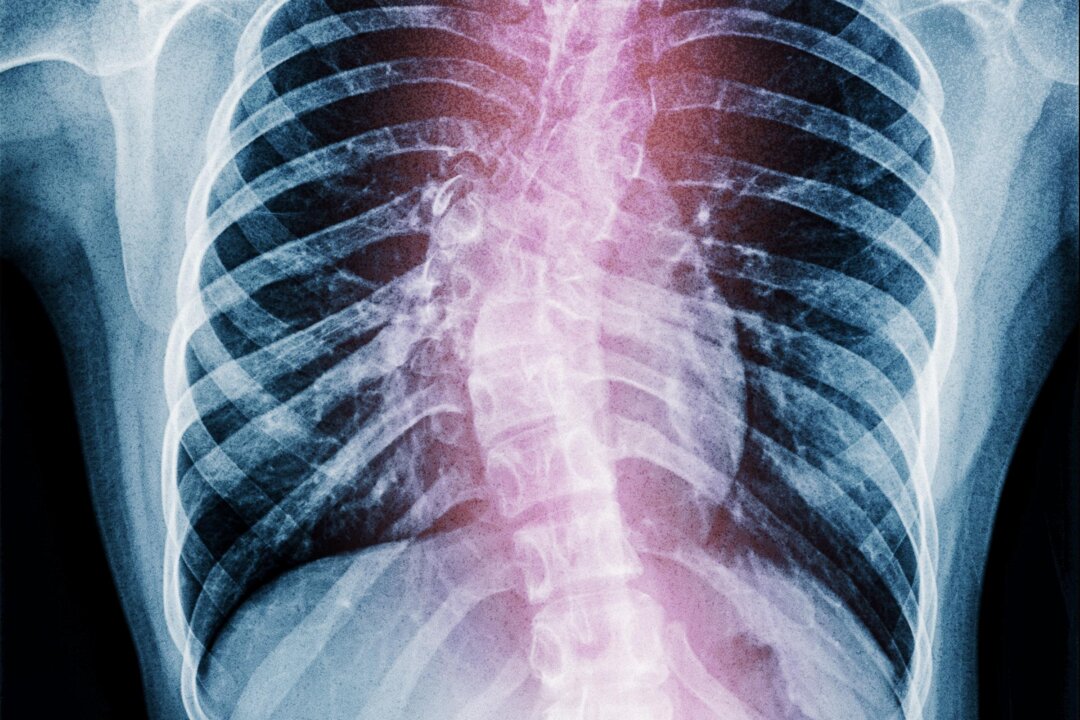

Unexplained lower back pain, uneven shoulders, and an unsteady gait may signal a serious issue: potential scoliosis. This spinal condition can progress silently, leading to severe complications, including breathing difficulties and compromised nerve function. Despite these risks, many individuals overlook early symptoms, often waiting until the problem escalates. However, experts emphasize that early detection is crucial, as even moderate scoliosis can typically be stabilized or improved with appropriate intervention.

Common signs of scoliosis include not only back pain but also physical imbalances, such as shoulders that appear uneven when viewed from the front. An increasingly unsteady gait can also indicate spinal misalignment, which may not seem alarming at first but can lead to more serious complications if left unaddressed.